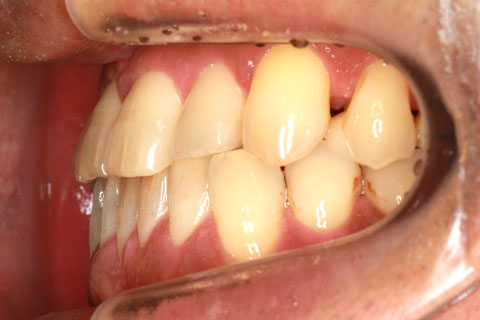

フルリンガル矯正2:上下の歯を舌側矯正で治療(矯正期間18ヶ月)

- 年齢・性別

- 42歳男性

- 治療期間

- 1年6ヶ月

- 抜歯

- なし

- 治療費

- 120万円(税込み)

- 備考

- マルチブラケットを用いた矯正治療

- 治療内容

- 反対咬合をフルリンガル矯正治療にて改善

- 施術の副作用(リスク)

- 表側矯正と比較して、歯根の角度を確立する「トルク」の力がかかりにくい。